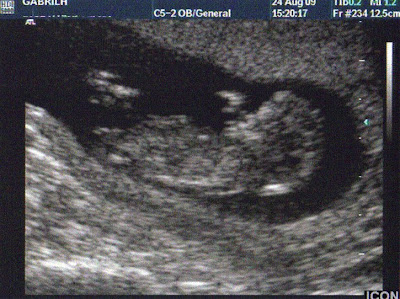

Θυμήθηκα πριν από λίγο ότι πέρσι τέτοια εποχή είδα για πρώτη φορά την Αθηνά σε υπέρηχο. Ο τότε γυναικολόγος μου δεν ήταν υπέρ των πολλών υπέρηχων με αποτέλεσμα να μην δω ποτέ τον περιβόητο… σάκο, να μην ακούσω καν καρδούλα.

Έγκυος 12 εβδομάδων είχαμε το πρώτο μας «ραντεβού» με το μωρό μας. Όταν την είδαμε στην οθόνη, ένα «ατσούμπαλο» ακόμα ανθρωπάκι τόσο δα μικρό, ξέσπασα σε λυγμούς (τι πρωτότυπο για μένα από τότε που έμεινα έγκυος!!).

Είχα πάθει το σοκ της ζωής μου… Ήξερα ότι είμαι έγκυος, αλλά τόσες βδομάδες με ανύπαρκτη κοιλιά και ένα έμβρυο τόσο μικρό που δεν ένιωθα τις κινήσεις του, δεν είχα συνηδειτοποιήσει ότι όντως κάτι… σχηματίζεται μέσα μου. Και όχι ότι και ότι… Ένα μωρό! Το δικό μας μωρό!